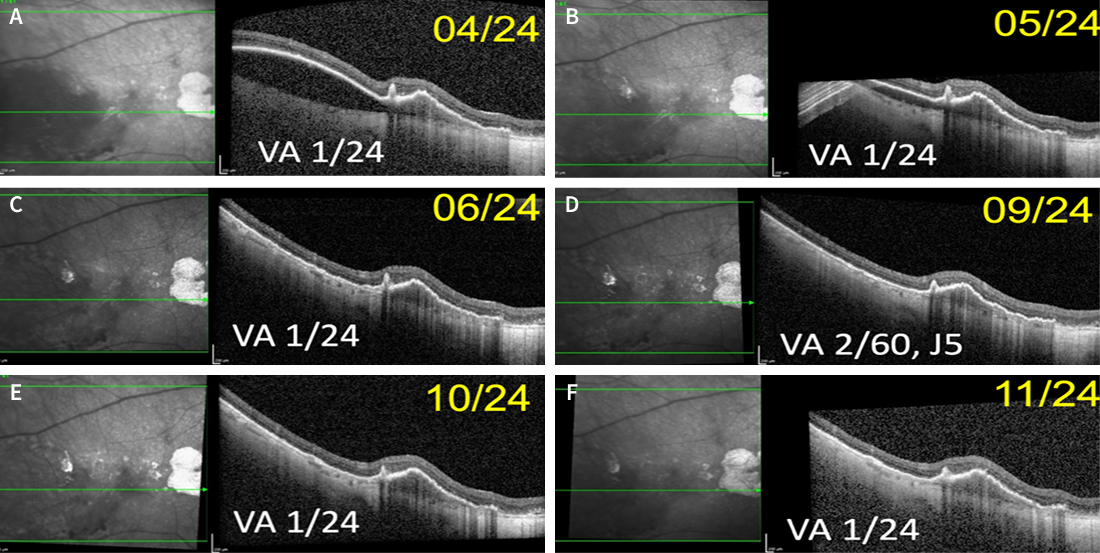

The patient was then followed in our clinic for routine monitoring of each eye in November 2023, January 2024, and March 2024 (Figure 5). As shown in Figure 5F, the patient developed sub-foveal bleeding in the left eye in March 2024. No treatment was offered for the left eye at that time, and the patient was directed to return in 1 month for continued monitoring. During this visit, in April 2024, the sub-foveal bleeding in the left eye demonstrated signs of resolution; however, for the right eye, the decision was made to restart anti-VEGF treatment. The patient was subsequently administered intravitreal aflibercept injections in April, May, and June 2024. OCT follow-up in the right eye is shown in Figure 6, and in the left eye in Figure 7.

<p>Figure 6. OCT follow-up of the patient’s right eye over time. Intravitreal aflibercept injections were administered in April, May, and June 2024. </p>

Figure 6. OCT follow-up of the patient’s right eye over time. Intravitreal aflibercept injections were administered in April, May, and June 2024.

<p>Figure 7. OCT follow-up of the patient’s left eye over time.  </p>

Figure 7. OCT follow-up of the patient’s left eye over time.